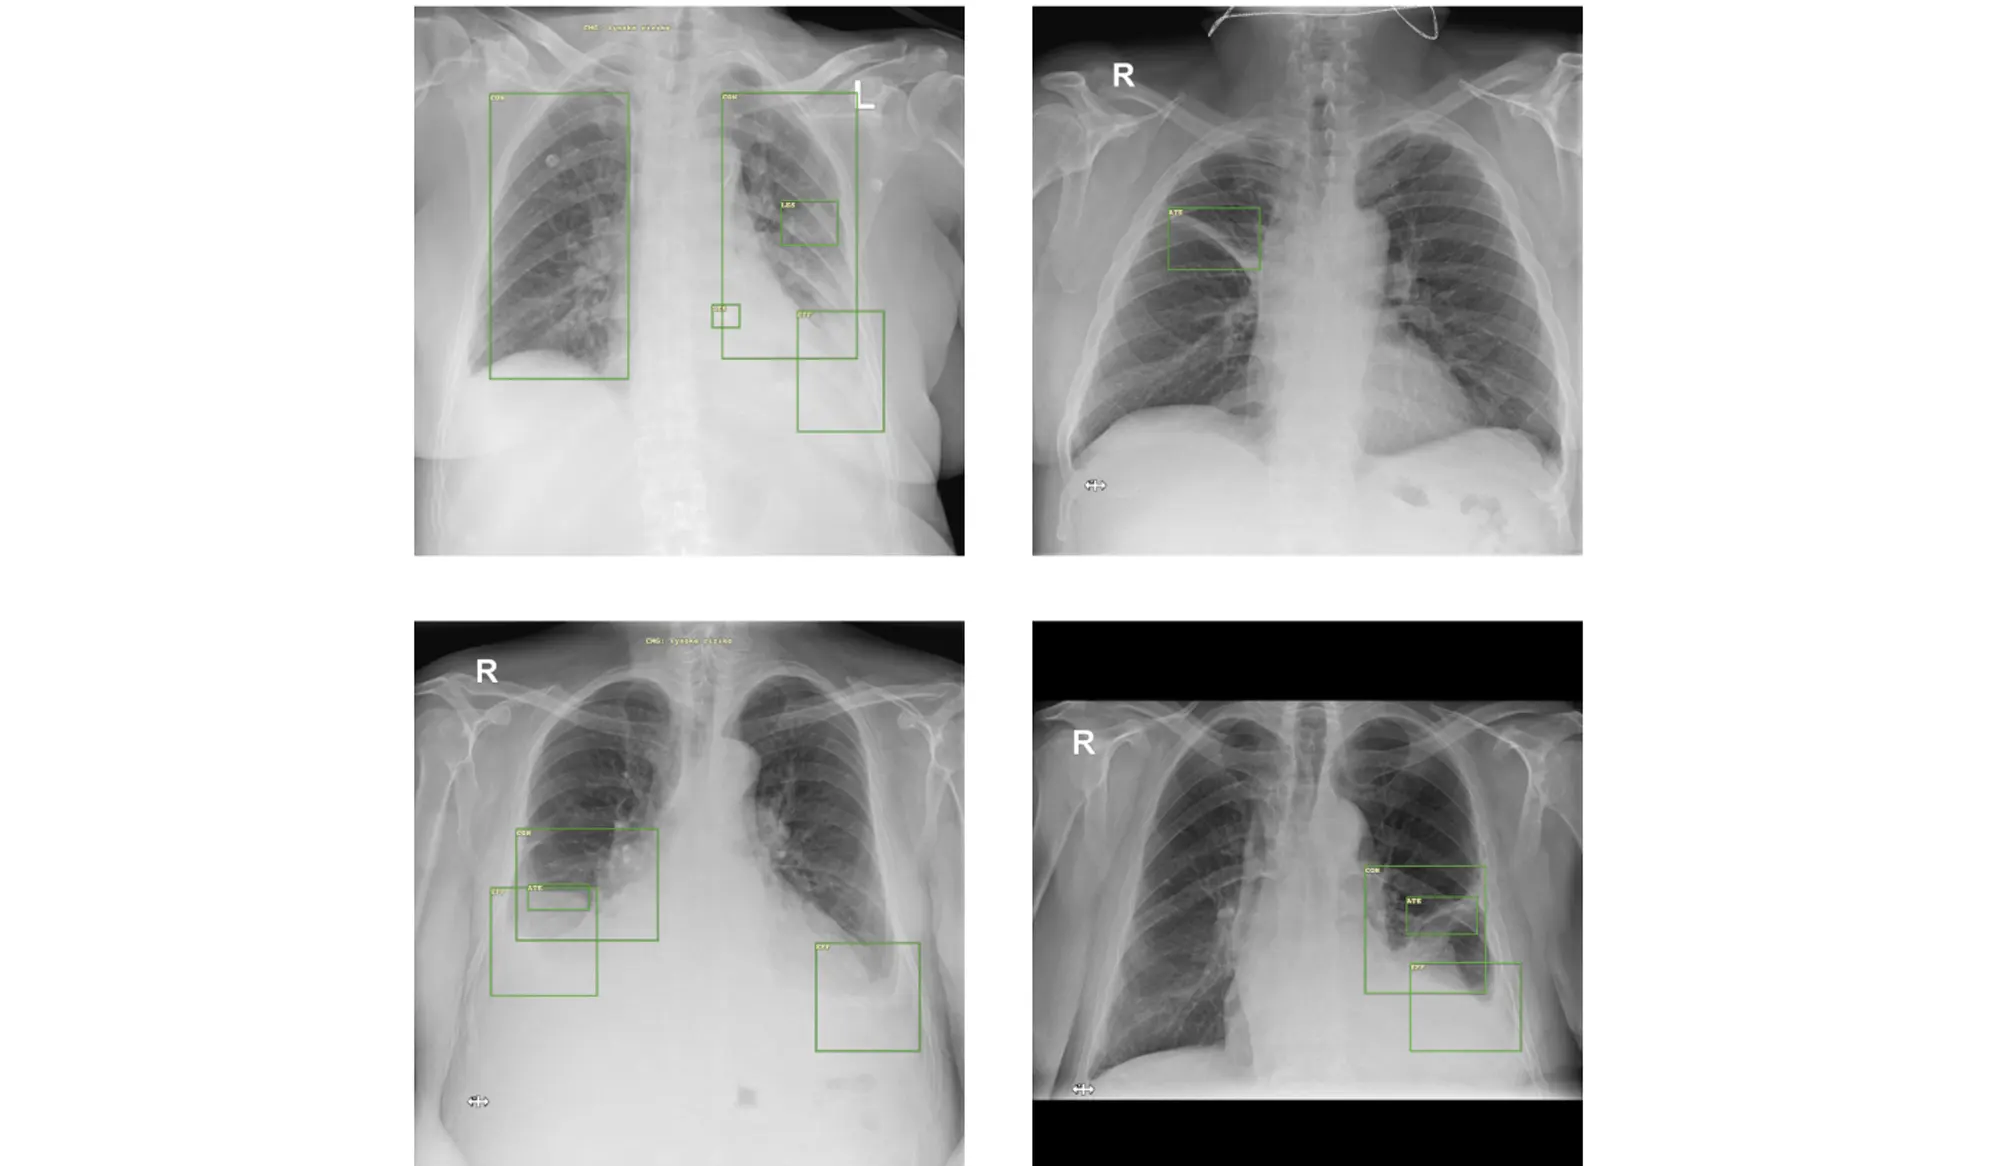

Chest X-ray (CXR) is considered to be the most widely used modality for detecting and monitoring various thoracic findings, including lung carcinomas and other pulmonary lesions. However, X-ray imaging shows particular limitations when detecting primary and secondary tumors, and are prone to reading errors due to limited resolution and disagreement between radiologists. To address these issues, we developed a deep learning-based automatic detection algorithm (DLAD) to automatically detect and localize suspicious lesions on CXRs. Five radiologists were invited to retrospectively evaluate 300 CXR images from a specialized oncology center, and the performance of individual radiologists was subsequently compared with that of DLAD. The proposed DLAD has achieved significantly higher sensitivity (0.910 (0.854-0.966)) than that of all assessed radiologists (RAD 1 0.290 (0.201-0.379), p<0.001, RAD 2 0.450 (0.352-0.548), p<0.001, RAD 3 0.670 (0.578-0.762), p<0.001, RAD 4 0.810 (0.733-0.887), p=0.025, RAD 5 0.700 (0.610-0.790), p<0.001). The DLAD specificity (0.775 (0.717-0.833)) was significantly lower than in all assessed radiologists (RAD 1 1.000 (0.984-1.000), p<0.001, RAD 2 0.970 (0.946-1.000), p<0.001, RAD 3 0.980 (0.961-1.000), p<0.001, RAD 4 0.975 (0.953-0.977), p<0.001, RAD 5 0.995 (0.985-1.000), p<0.001). The study results demonstrated that the proposed DLAD could be utilized as a decision-support system to reduce radiologists' false negative rate.